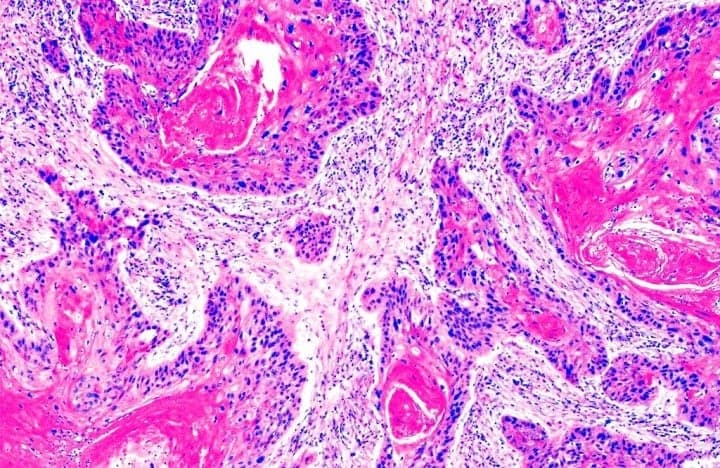

Плоскоклітинна метаплазія — це зміна типу клітин, яка зазвичай вважається передраковим станом. Це процес, коли звичайні клітини епітелію перетворюються на плоскоклітинні. Така зміна може відбуватися в різних органах. І хоча вона потенційно може призвести до раку, це не завжди є невідворотним.

Лікарі використовують різноманітні методи для виявлення та моніторингу метаплазії. Це може бути біопсія, цитологічний аналіз, або сучасні інструментальні підходи, такі як МРТ чи КТ.

- Біопсія

- Цитологічний аналіз